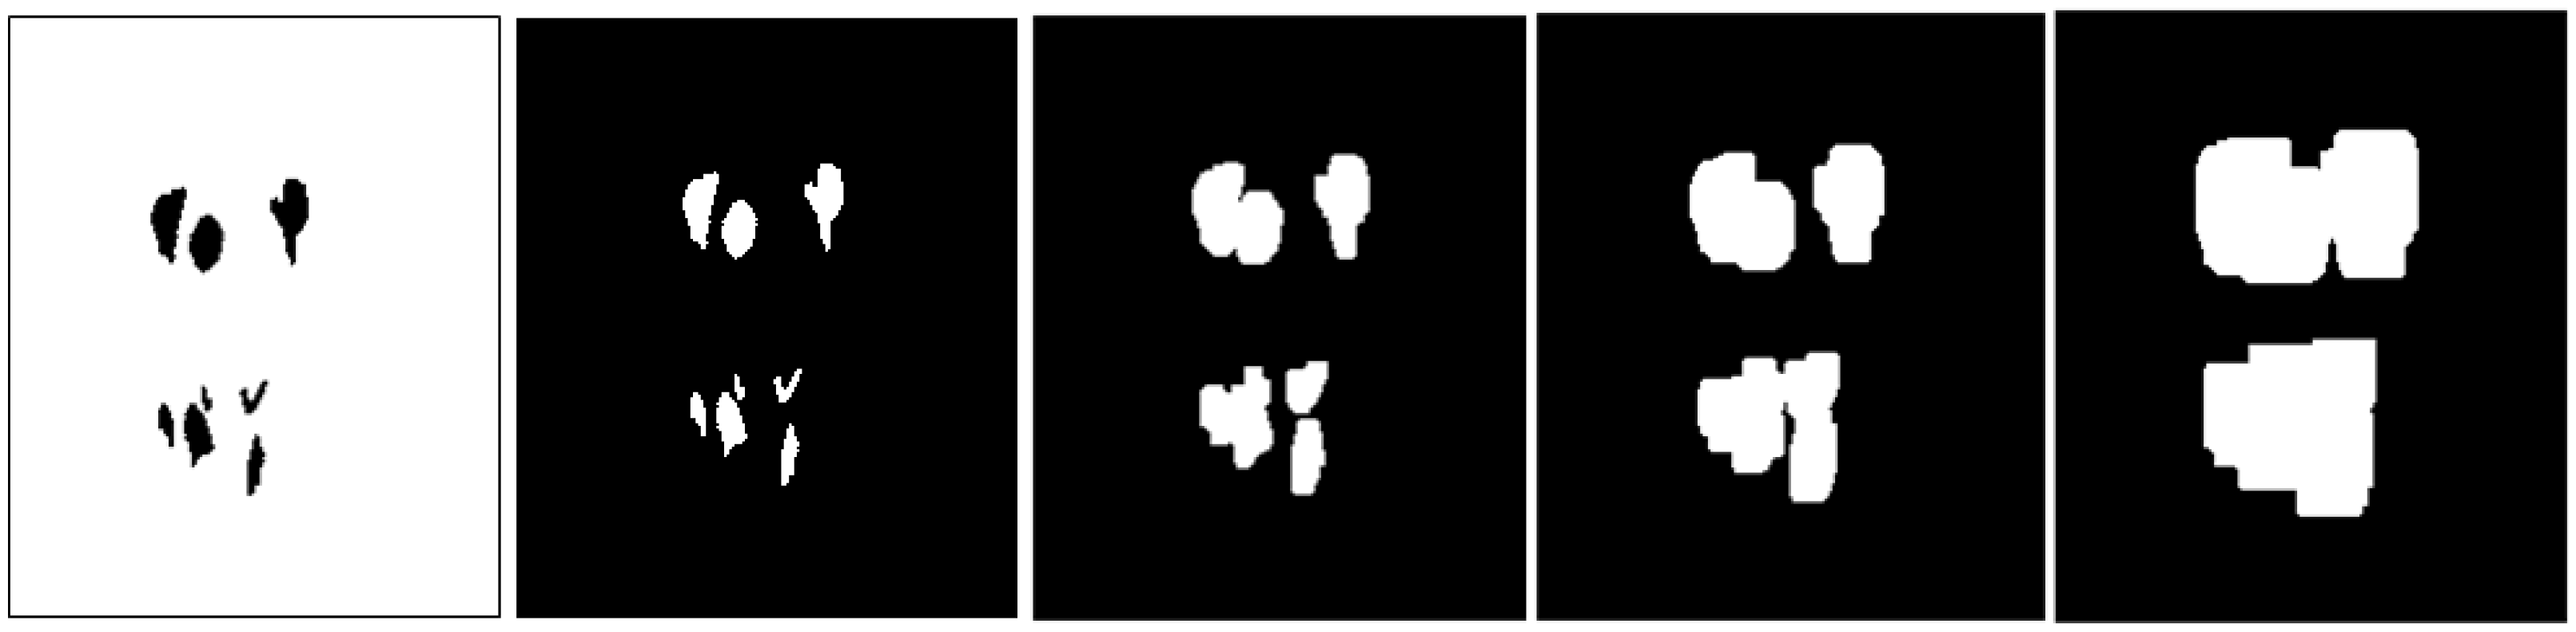

2.1. CNUH Dataset and Challenges